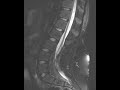

Tethered Cord

These images demonstrate low termination of the spinal cord which is thinned and plastered against the dorsal aspect of the thecal sac at the L3-L4 level. There is a tiny cord syrinx distally and mild diffuse T2 hyperintensity of the distal cord compatible with myelomalacia. There is a small focus of intradural fat posteriorly at the terminal aspect of the cord which is best seen on the T1 weighted images.There are very prominent fat filled epidural spaces which narrow the spinal canal. This patient has a history of lipomyelomeningocele which was repaired and presented with increased lower extremity numbness secondary to retethering of the cord. Lipomyelomeningocele is a closed spinal dysraphism where meninges and the neural placode herniate through the dysraphism into the subcutaneous lipoma.